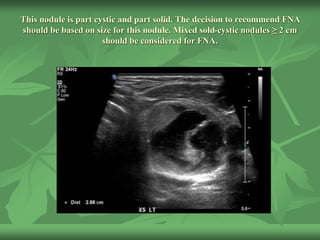

This nodule is part cystic and part solid. The decision to recommend FNA

should be based on size for this nodule. Mixed sold-cystic nodules ≥ 2 cm

should be considered for FNA.